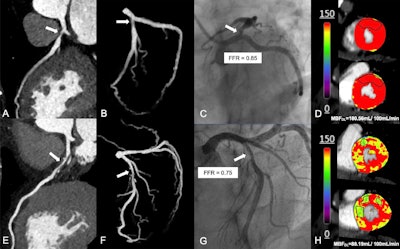

Representative images from diagnostic analysis of deep learning (DL)-based CT myocardial perfusion imaging (MPI). (A-D) Representative images in a 51-year-old woman with stable angina at presentation. (A) Curved planar reformation and (B) three-dimensional maximum intensity projection images show severe stenosis of the opening left anterior descending artery (arrow). (C) Fractional flow reserve (FFR) determined with invasive coronary angiography helps confirm that there was no hemodynamic significance of the opening left anterior descending artery lesion (arrow). (D) Dynamic CT MPI provided functional information to identify hemodynamically significant stenosis with reference to invasive FFR. Myocardial blood flow (MBF) derived from DL-based CT MPI revealed the absence of decreased myocardial perfusion of the left anterior descending artery territory (the areas outlined in black represent the myocardium subtended by the left anterior descending stenosis, and the color bar is a graphical scale that maps MBF ranges). (E-H) Representative images in a 62-year-old man with exertional chest pain at presentation. (E) Curved planar reformation and (F) three-dimensional maximum intensity projection images show moderate stenosis of the middle left anterior descending artery (arrow). (G) FFR determined at invasive coronary angiography helps confirm that the middle left anterior descending lesion was hemodynamically significant (arrow). (H) Dynamic CT MPI provided functional information to identify hemodynamically significant stenosis with reference to invasive FFR. DL-based CT MPI showed a reduction in MBF within the middle and basal anterior wall of the left anterior descending artery territory (the areas outlined in black represent the myocardium with decreased perfusion, and the color bar is a graphical scale that maps MBF ranges). MBFDL = MBF derived from the DL model.Radiology and the RSNA

Representative images from diagnostic analysis of deep learning (DL)-based CT myocardial perfusion imaging (MPI). (A-D) Representative images in a 51-year-old woman with stable angina at presentation. (A) Curved planar reformation and (B) three-dimensional maximum intensity projection images show severe stenosis of the opening left anterior descending artery (arrow). (C) Fractional flow reserve (FFR) determined with invasive coronary angiography helps confirm that there was no hemodynamic significance of the opening left anterior descending artery lesion (arrow). (D) Dynamic CT MPI provided functional information to identify hemodynamically significant stenosis with reference to invasive FFR. Myocardial blood flow (MBF) derived from DL-based CT MPI revealed the absence of decreased myocardial perfusion of the left anterior descending artery territory (the areas outlined in black represent the myocardium subtended by the left anterior descending stenosis, and the color bar is a graphical scale that maps MBF ranges). (E-H) Representative images in a 62-year-old man with exertional chest pain at presentation. (E) Curved planar reformation and (F) three-dimensional maximum intensity projection images show moderate stenosis of the middle left anterior descending artery (arrow). (G) FFR determined at invasive coronary angiography helps confirm that the middle left anterior descending lesion was hemodynamically significant (arrow). (H) Dynamic CT MPI provided functional information to identify hemodynamically significant stenosis with reference to invasive FFR. DL-based CT MPI showed a reduction in MBF within the middle and basal anterior wall of the left anterior descending artery territory (the areas outlined in black represent the myocardium with decreased perfusion, and the color bar is a graphical scale that maps MBF ranges). MBFDL = MBF derived from the DL model.Radiology and the RSNA